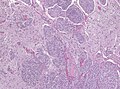

|

Meningioma. HPS stain. | |

Microscopic

Features (memory device WCN):

- Whorled appearance - key feature.

- Calcification, psammomatous (target-like appearance; (tight) onion skin).

- +/-Nuclear pseudoinclusions - focal nuclear clearing with a sharp interface to unremarkable chromatin.